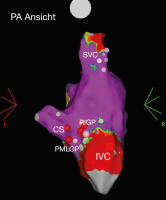

Elektroanatomisches Voltage-Mapping

Abbildung 2: Elektroanatomisches Voltage-Map vom rechten Atrium, Ansicht aus posterior-anterior (PA). Zu sehen sind die Ablationsimpulse am rechten inferioren Ganglienplexus (RIGP) sowie am posteromedialen linken Ganglienplexus (PMLGP). CS: Koronarsinus, IVC: inferiore Vena cava, SVC: superiore Vena cava

Keywords: AblationElektroanatomisches Voltage-MappingKardiologie